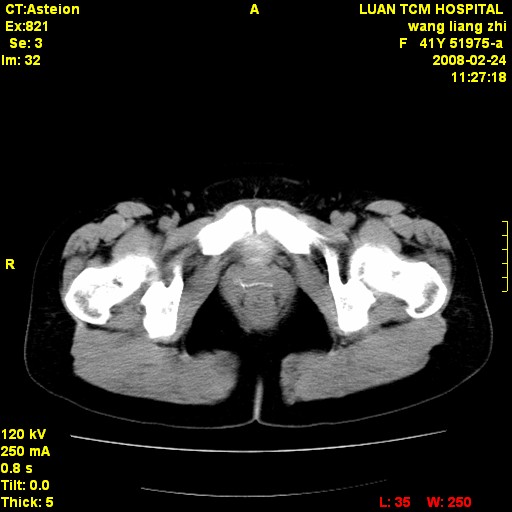

以下是引用dyqct在2009-8-23 16:17:00的发言:[br]考虑:1、造影剂进入腹腔、结肠旁沟、肝周;[br] 2、子宫明显增大(腺肌增生症?);[br] 3、膀胱显影是由于造影剂吸收后经肾分泌进入膀胱的;[br] 4、建议mri检查子宫。